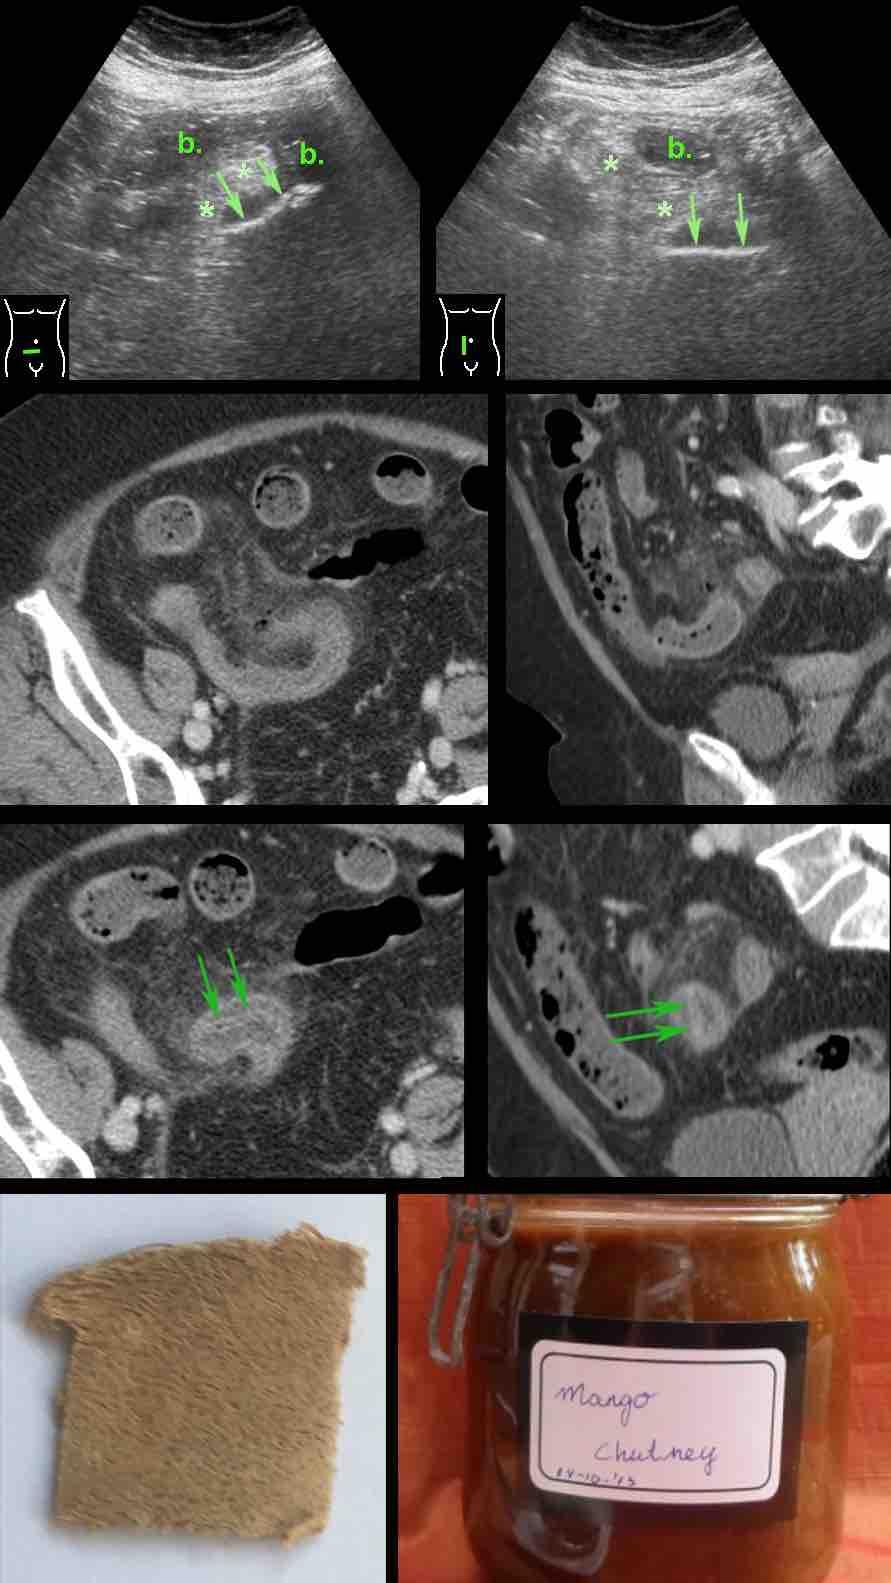

Bệnh nhân nữ béo phì 80 tuổi với nghi ngờ lâm sàng mạnh về viêm ruột thừa.

Tiền sử cắt túi mật.

Xét nghiệm: bạch cầu 21, CRP 125.

Siêu âm cho thấy mỡ viêm (*) xung quanh quai ruột non phù nề (b.), chứa một cấu trúc phản âm bất thường (mũi tên).

Hình ảnh siêu âm trên hai mặt phẳng vuông góc gợi ý dị vật này có bản chất dẹt.

CT xác nhận dày thành ruột non, hình ảnh mờ mỡ và khí ngoài lòng ruột.

Quan sát kỹ hơn trên mặt phẳng axial và coronal của CT, phát hiện một cấu trúc dẹt hai lớp, hơi tăng tỷ trọng (mũi tên) nằm trong lòng ruột, nguồn gốc chưa rõ.

Phẫu thuật phát hiện tổn thương loét khu trú ruột non do một mảnh vỏ rau quả sắc cạnh.

Sau phẫu thuật, bệnh nhân nhận ra đây là vỏ của quả xoài xanh, được dùng trong món mứt xoài tự làm của bà.